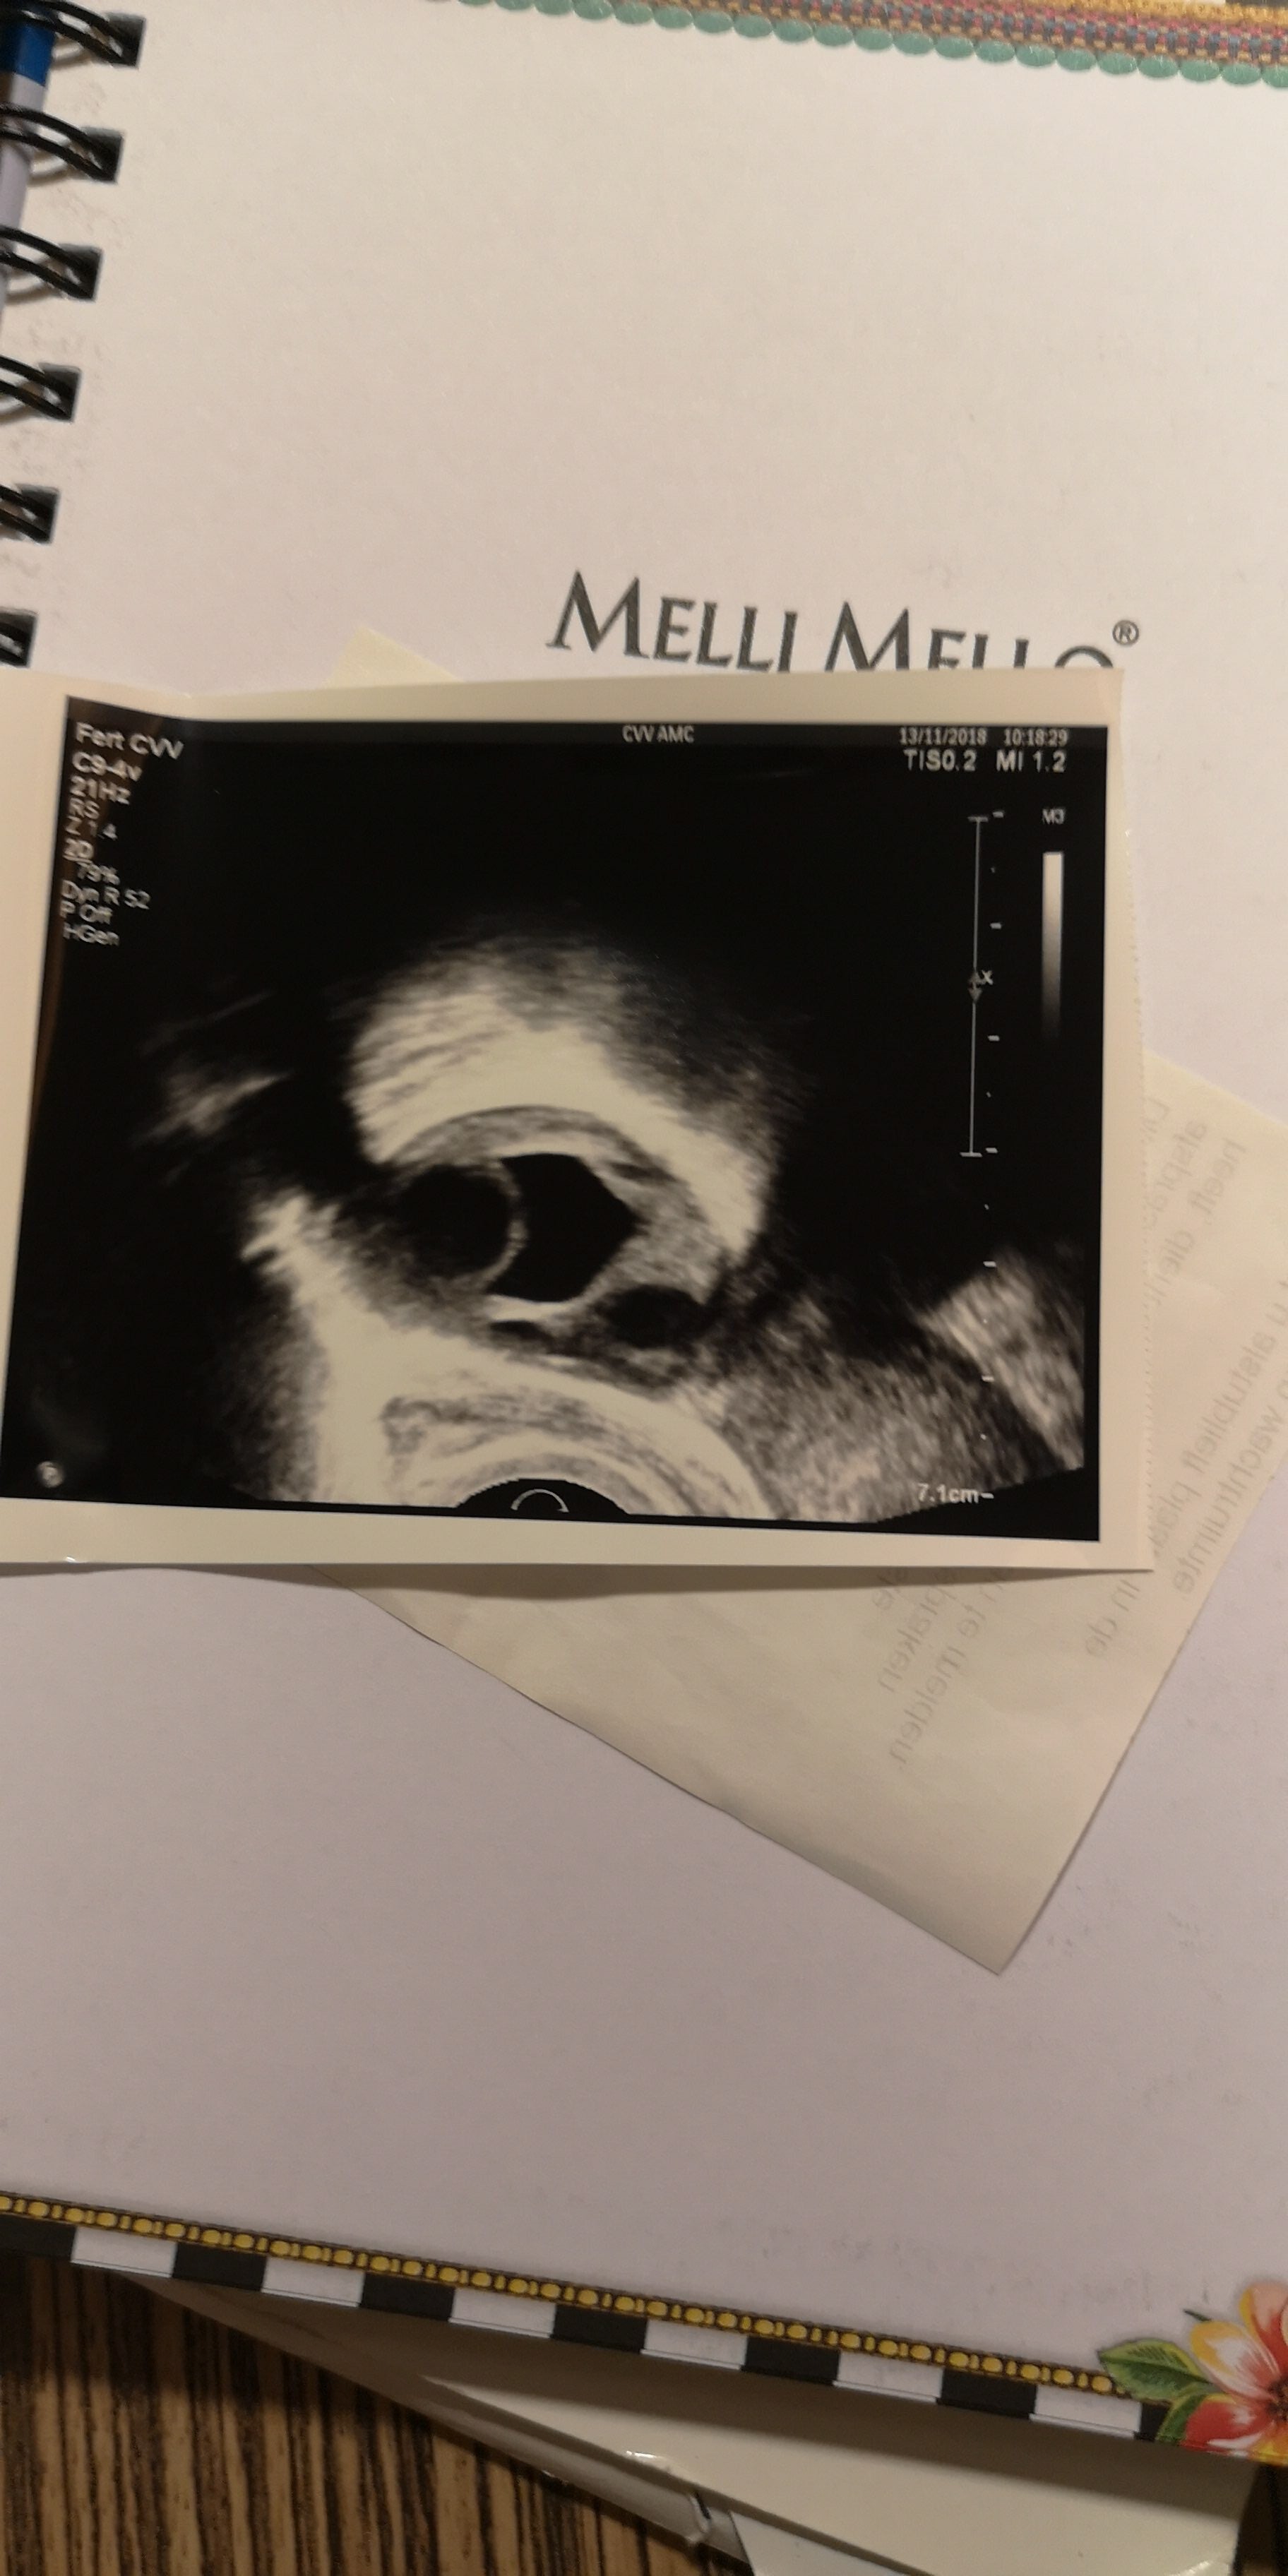

Ik moest voor deze behandeling heel vaak naar het AMC voor echo’s, als je een preuts persoon bent ben je dat echt niet meer na deze procedure. Nog nooit zoveel mensen die mij ontbloot met me benen wijd hebben zien liggen haha. Voor deze behandeling kreeg ik een injectie naald waarmee ik mezelf moest prikken. In die injectie zaten hormonen waardoor mijn eiblaasjes sneller zouden gaan groeien. Ik moest eerst wachten op een menstruatie, als dit eenmaal klaar was kon ik gaan beginnen met injecteren. Elke avond om dezelfde tijd. En aangezien ik kanker had werd me ook gevraagd mee te doen aan een onderzoek. Voor dit onderzoek moest ik elke avond een tabletje innemen. Dit tabletje zou ervoor moeten zorgen dat er een soort laagje over de tumor heen kwam te liggen waardoor de hormonen er niet bij zouden kunnen. Want ja het is natuurlijk wel een hormoongevoelige tumor en ik zou me een aantal weken lang helemaal volspuiten met die zooi.

Om te kijken of me eiblaasjes al goed aan het groeien waren moest ik op een gegeven moment om de dag ofzo in het ziekenhuis zijn. Dan moest ik eerst bloed laten prikken vanwege dat onderzoek en daarna werd er nog een echo gemaakt. Vaak duurde dit maar 5 minuten en kon ik weer gaan. Op het moment dat mijn eiblaasjes bijna groot genoeg waren om te oogsten kreeg ik er nog een 2de injectie bij. Deze zou ervoor zorgen dat ik geen eisprong kreeg. 36 uur geloof ik voor de eiceloogst moest ik mezelf een injectie geven die er juist voor zorgt dat er een eisprong plaats zou vinden waardoor de eitjes gemakkelijk weg te halen waren.